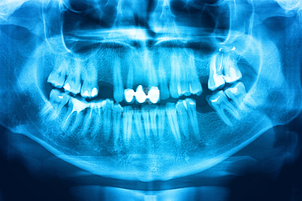

Por su parte el odontólogo revisará la historia clínica del paciente y le realizará algunas preguntas. Luego el ortodoncista efectuará una completa revisión bucodental, en la que evaluará el estado de los tejidos adyacentes al diente, las encías y todo lo relacionado a la salud periodontal, con la finalidad de realizar un diagnóstico y le da al periodoncista un panorama de la situación oral del paciente.

Así mismo, se le realizarán radiografías y se le tomarán fotos para tener una completa recopilación multimedia de la enfermedad y para evaluar el nivel de pérdida ósea, así como también la detección de lámina dura, las modificaciones dentales debido a la periodontitis o es estudio de la morfología radicular.